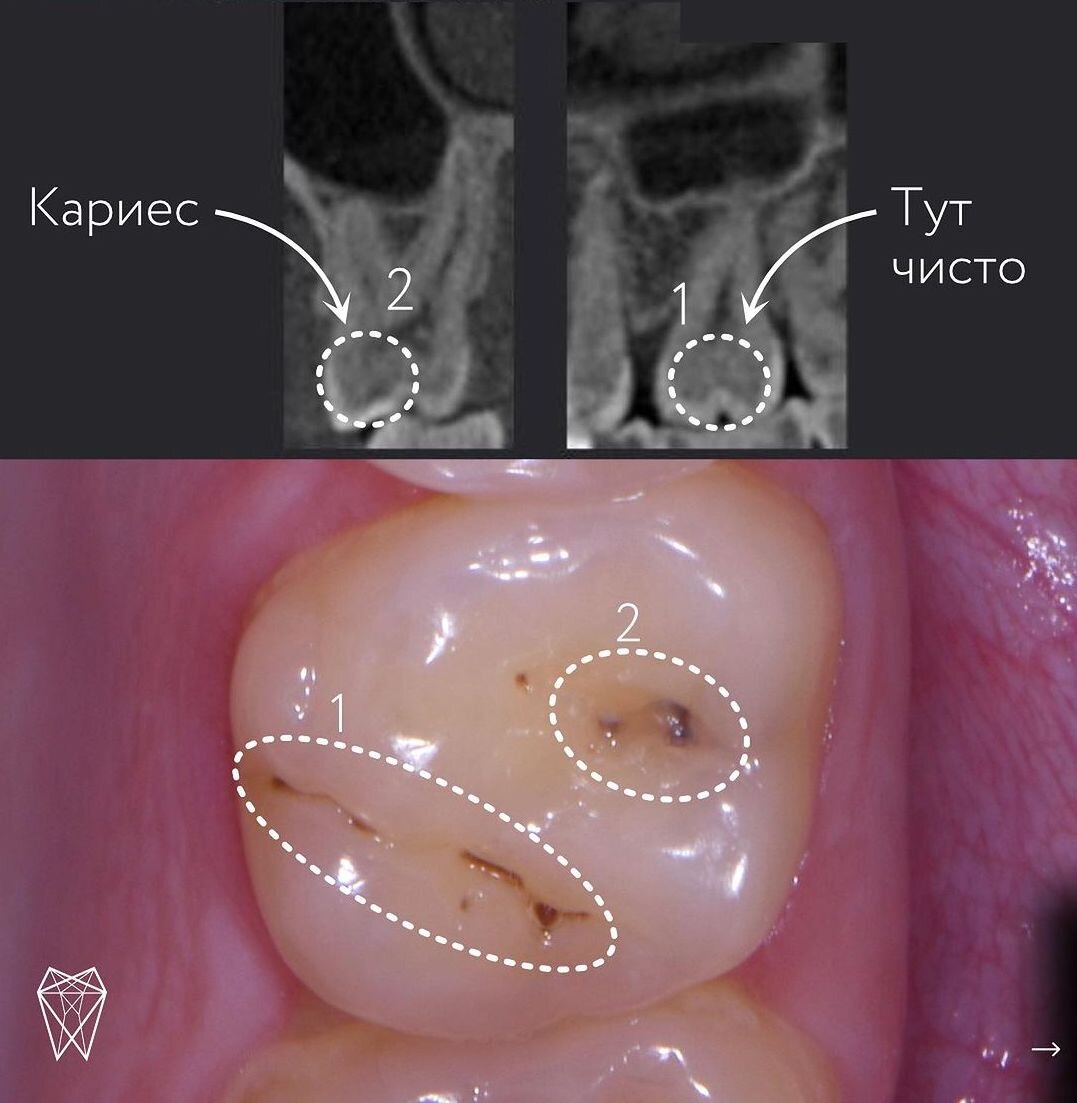

Случай из практики: кариес или естественная пигментация?

Cтоматолог-терапевт проводит точную диагностику с помощью искусственного интеллектом Diagnocat, чтобы определить, какие темные пятна на зубе - кариес, а какие - просто естественная пигментация фиссур.

Давайте посмотрим на кейс стоматолога-терапевта Агаты Касаткиной.

А это - естественная пигментация фиссур.